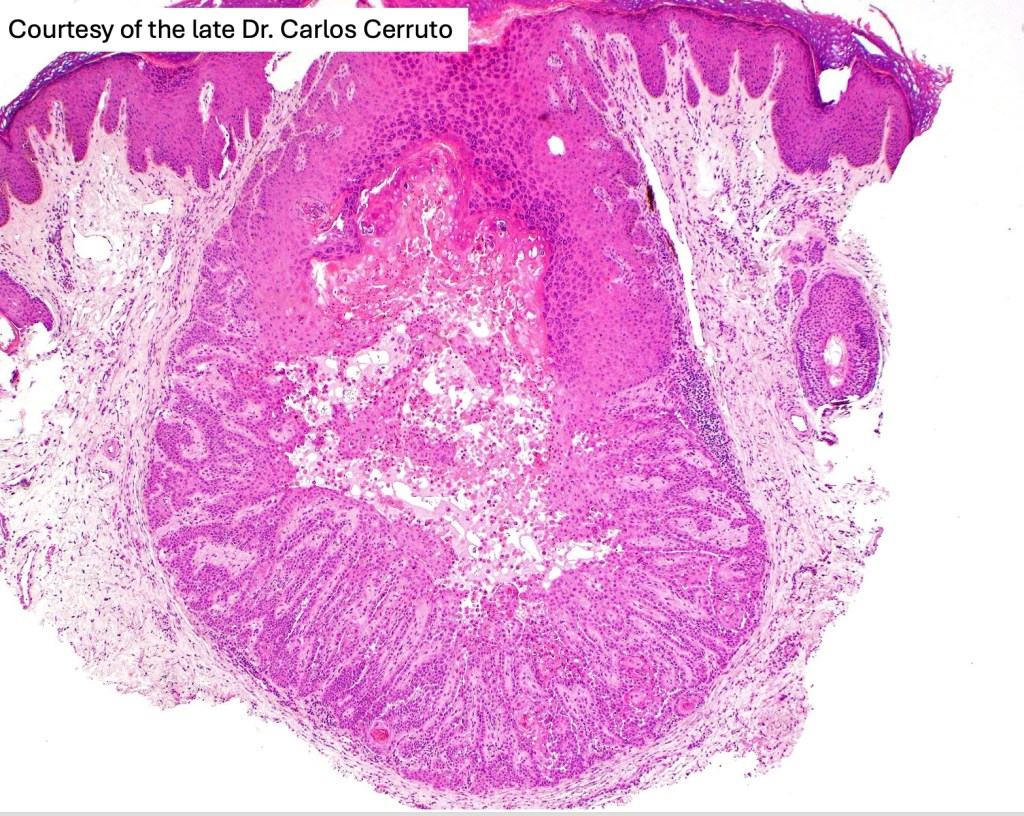

Warty dyskeratoma

•Umbilicated solitary nodule on sun-damaged skin of the head & neck but may arise elsewhere

•Rarely multiple lesions are present

•Follicular continuity often evident

•Cup-shaped, cystic invagination containing keratinous debris showing conspicuous corps ronds & grains of Darier

•The deeper reaches show acantholysis and prominent suprabasal villi